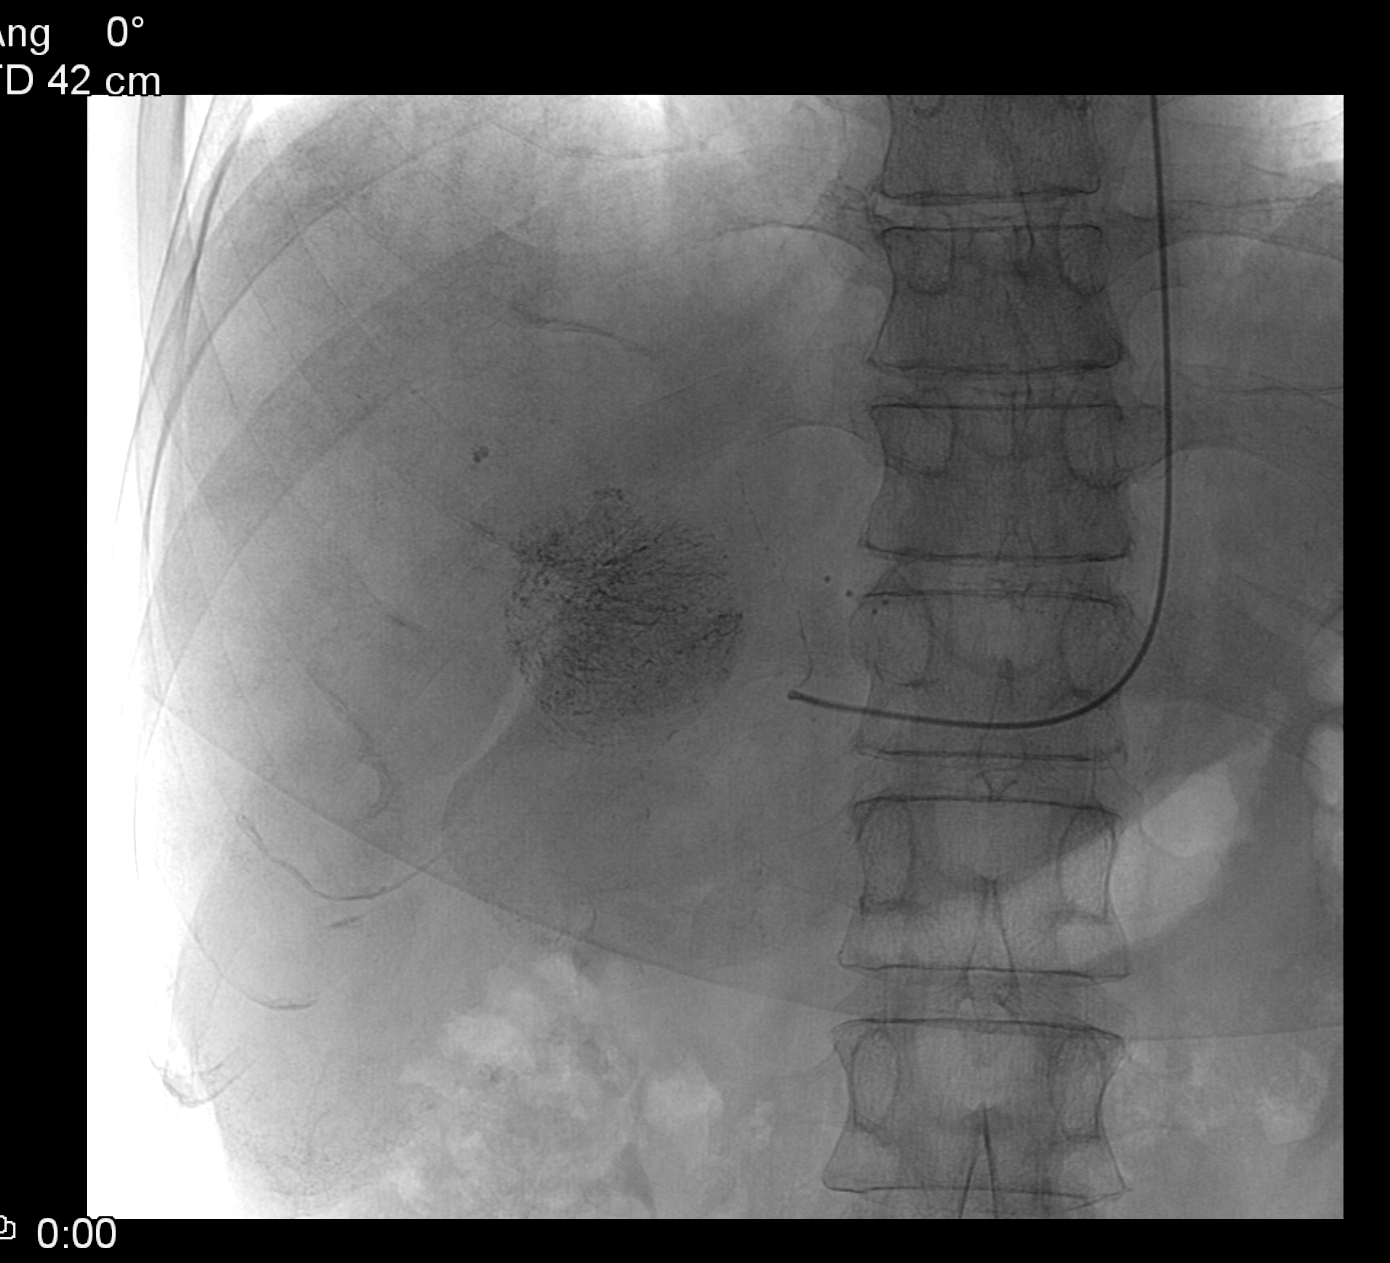

Concerning the HCC, the knowledge of history is very important for the decision and usually the oncoteams consider the performance of an imaging modality guided biopsy basically important for the further therapeutic decisions (because of the hystological validation rather core biopsy should be performed! (Figure 26, 27, 28).

Figure 26: HCC, verified with FNAB, US

Figure 27: HCC, TAE, agniography

Figure 28: HCC, native CT after TAE